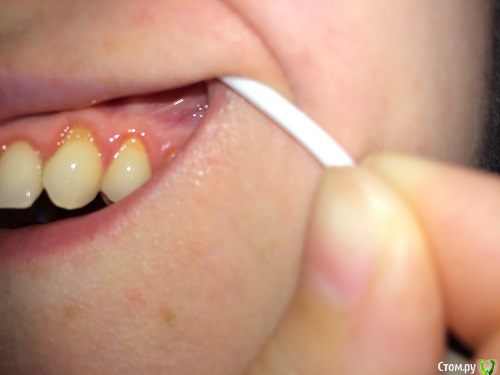

lalafa Опубликовано 16 августа, 2017 Поделиться Опубликовано 16 августа, 2017 (изменено) Здравствуйте, помогите, пожалуйста, советами.Мне 29 лет. Хронические заболевания - гранулезный фарингит, гастрит, ГЭРБ, сколиоз. У меня генерализованная рецессия десны, катаральный гингивит, пародонтальных карманов нет. Рекомендовано ортодонтическое лечение. НО ортодонты предупредили, что велика вероятность продолжения рецессии десны во время лечения и ухудшения ситуации. Посетила 2 пародонтологов, мнения противоположные. Один рекомендует операцию по закрытию рецессии методом пересадки трансплантата с неба. Хочет оперировать до ортодонт лечения самые проблемные зубы - клыки на нижней челюсти и 4ку. Мотив - утолщить десну, чтобы она выдержала брекеты и не рецессировала еще больше.Другой пародонтолог говорит, что так как именно эти зубы "не стоят в зубной дуге" (цитата врача) трансплантат с неба не приживется и результата не будет. Советует делать операцию после снятия брекетов на прямые зубы.Вопросы:1) Насколько в принципе опасно при такой рецессии проводить ортодонтическое лечение? зубы могут расшатываться и выпасть в процессе лечения?2) Закрывать рецессию до брекетов или после? Действительно, на таких вывернутых зубах не приживается трансплантат?3) Постоянно мучаюсь с катаральным гингивитом. Прохожу Проф чистку раз в 6 месяцев, но без толку. за чистотой слежу и самостоятельно, но скученные зубные ряды все равно провоцируют гингивит. Можно надеяться, что после брекетов гингивит вылечится? Изменено 16 августа, 2017 пользователем lalafa Ссылка на комментарий

lalafa Опубликовано 17 августа, 2017 Автор Поделиться Опубликовано 17 августа, 2017 Про гигиену чищу зубы как показал стоматолог, по схеме.Нитью больно пользоваться, потому что сильная скученность.После проф чистки гингивит все равно есть, просто десны не кровоточат, но они красные и припухшие. фото сделаны после недели применения ополаскивателя, от которого сильно желтеют зубы, поэтому такой вид, как будто проблемы с гигиеной.Скажите. пожалуйста, на снимке есть признаки пародонтоза? Ссылка на комментарий